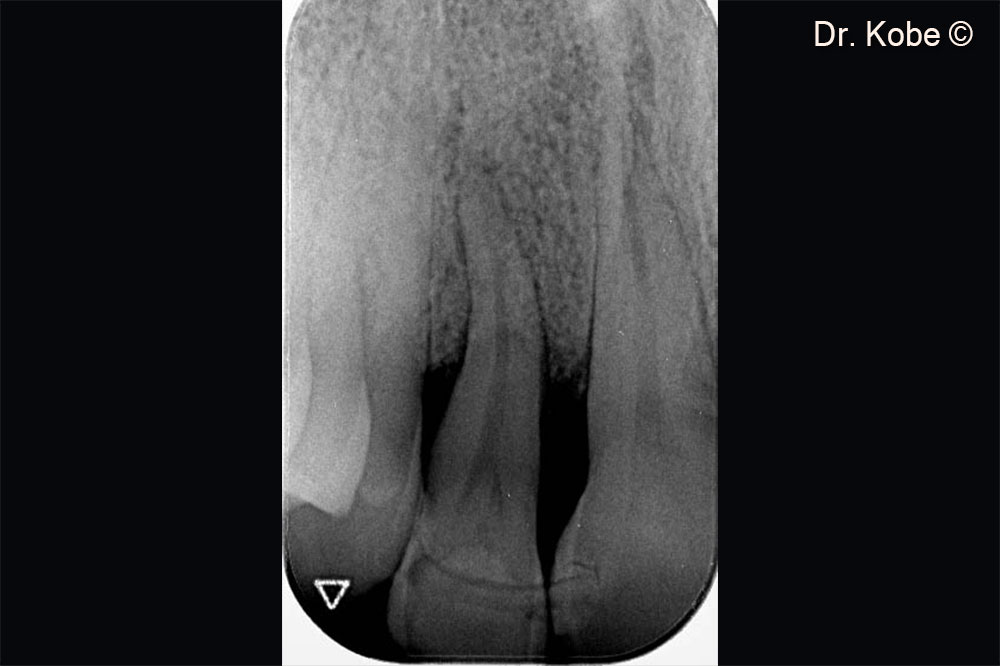

Khuyết tật xương theo chiều dọc trên phim chụp X-Quang